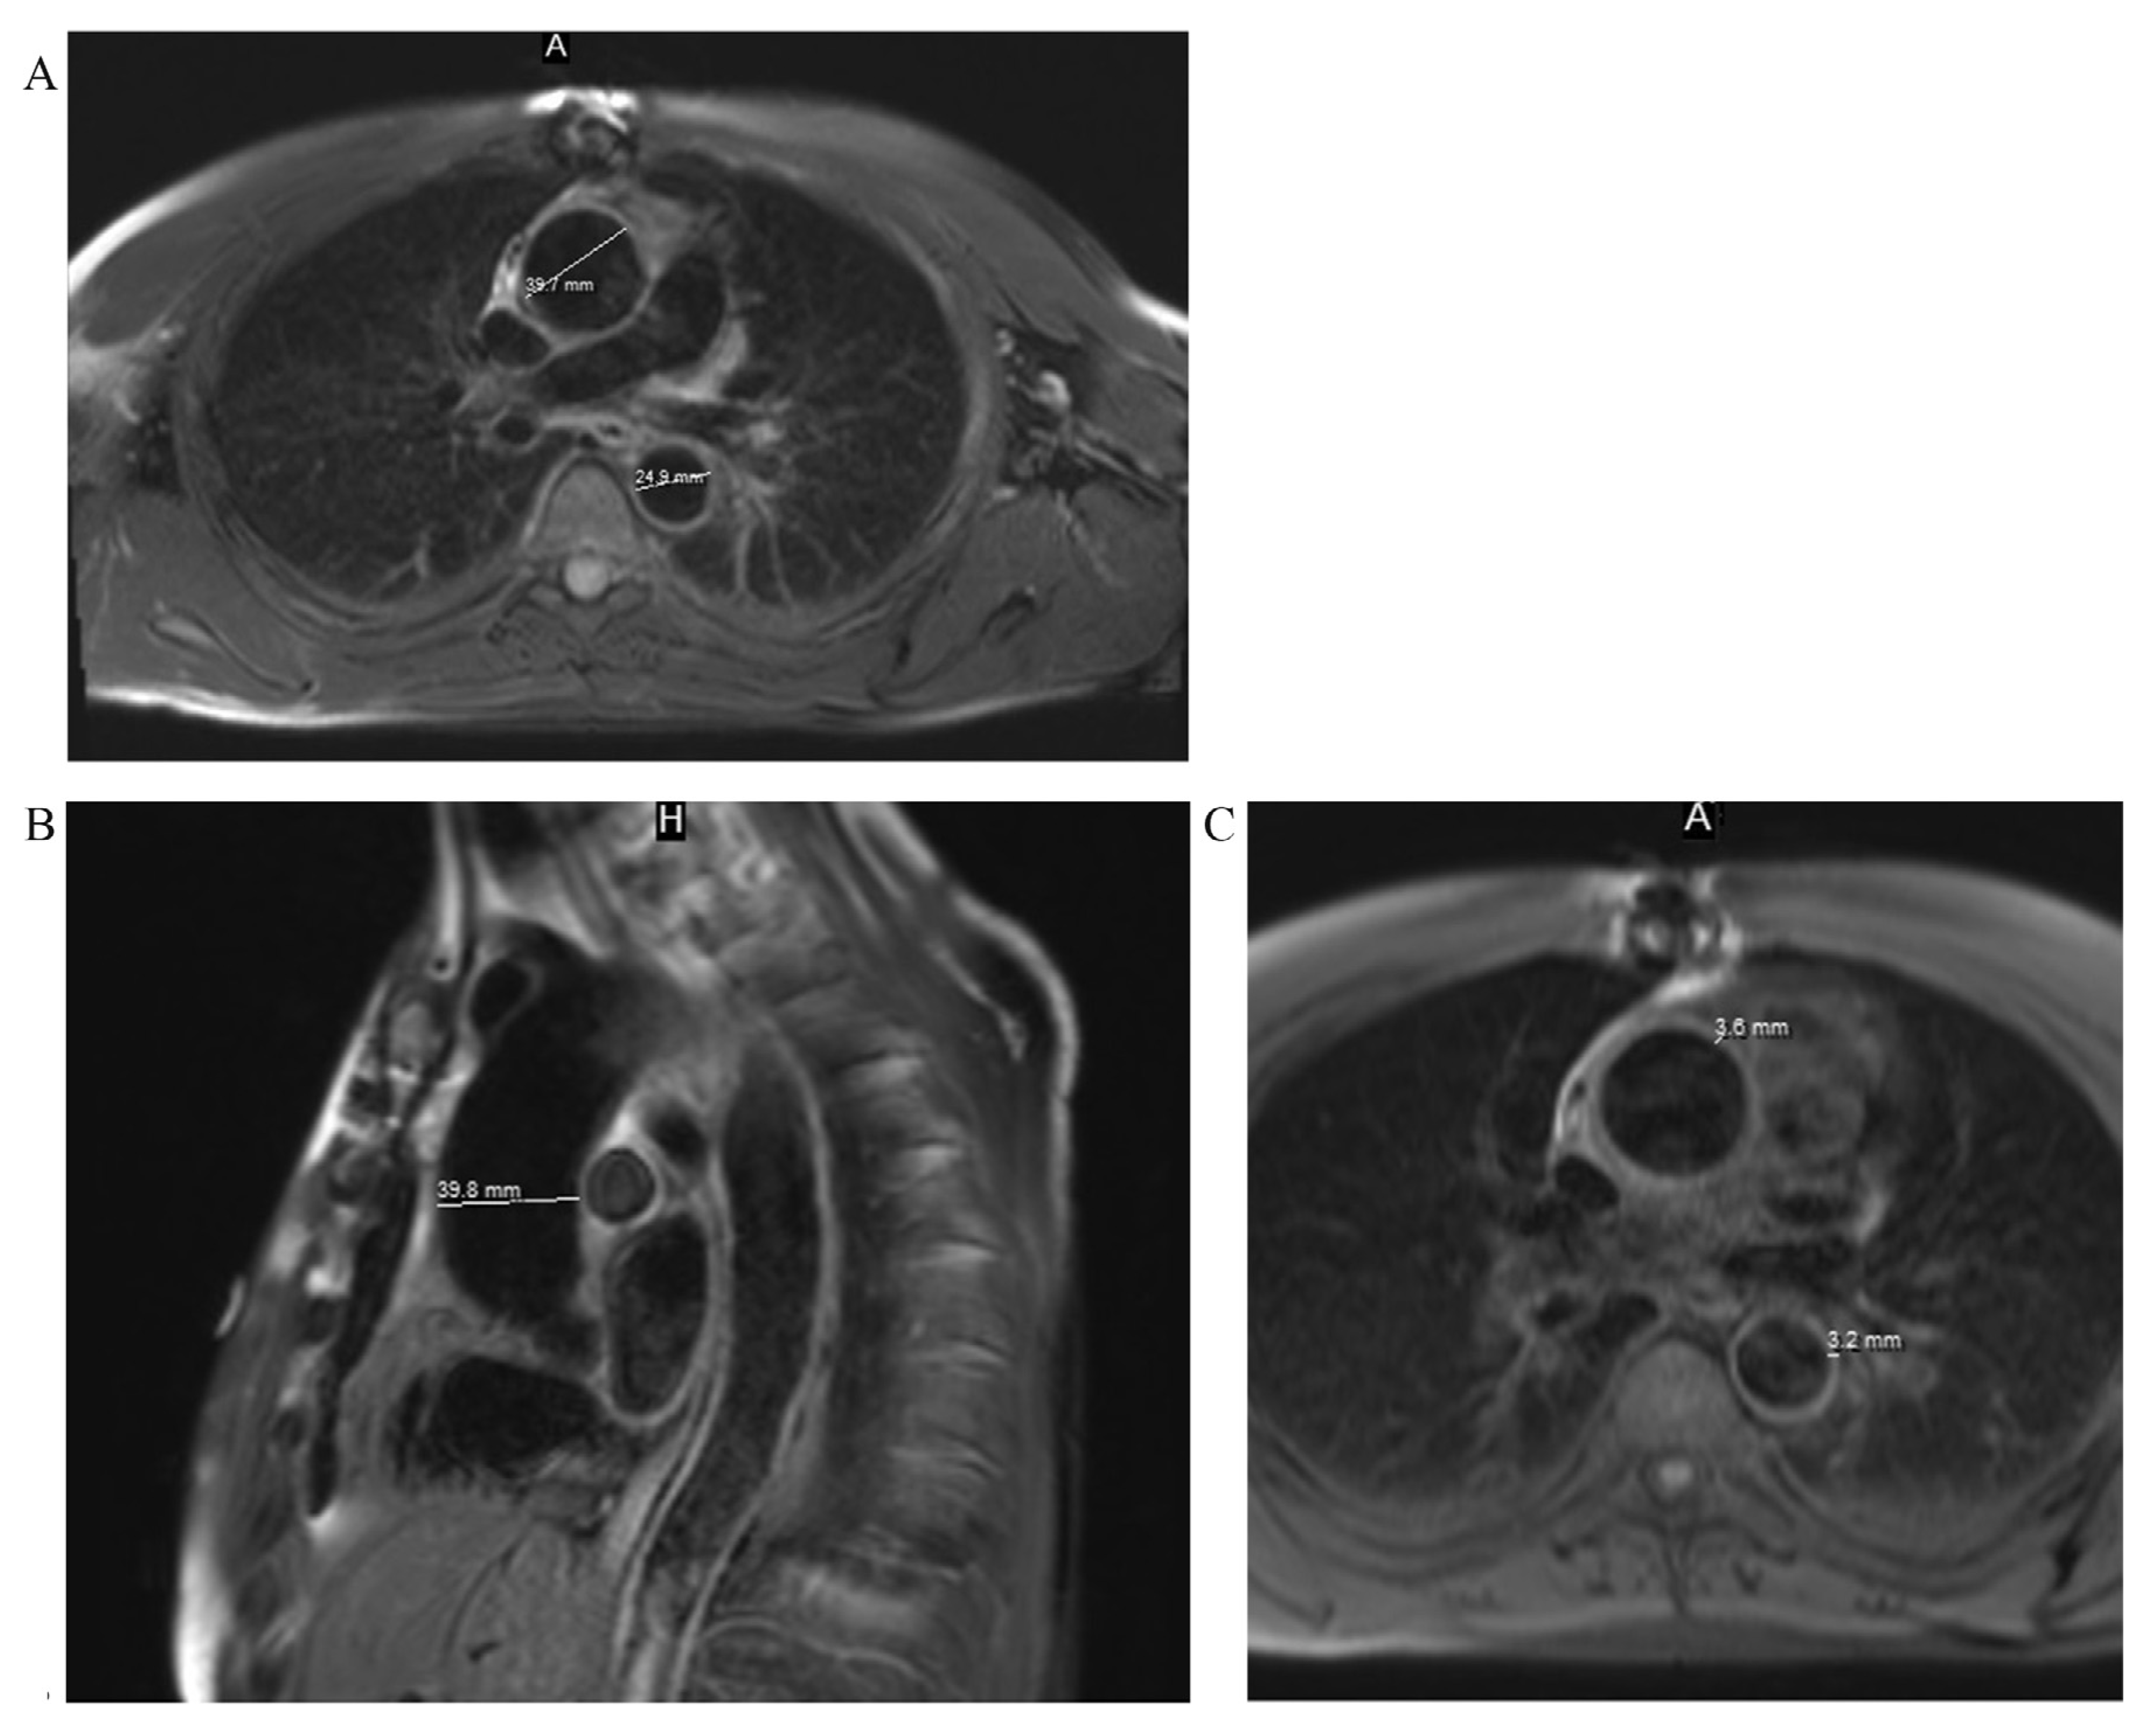

Moreover, aortic magnetic resonance imaging (MRI) was performed to measure diameters of entire thoracic aorta and for the assessment of aortic wall morphology. Thickened walls (3–3.6 mm) of the ascending and descending parts of aorta were noted. Subsequent parameters of thoracic aorta were obtained: aortic annulus, 22 mm (3-chamber view); aortic sinuses, 35 mm (3-chamber view); ascending aorta in the proximal and middle, 1/3 40 mm; distal, 1/3 39 mm; aortic arch in the T1 segment, 33 mm; T2 segment, 28 mm; and descending aorta, 25 mm (Fig. 5).

Fig. 5. - MRI views. A, a dilatation of the ascending part of the aorta in T2W FS axial view; B, a dilatation of the ascending part of the aorta in T2W FS sagittal view; C, thickened walls of the ascending and descending parts of the aorta in T1W FS axial view.